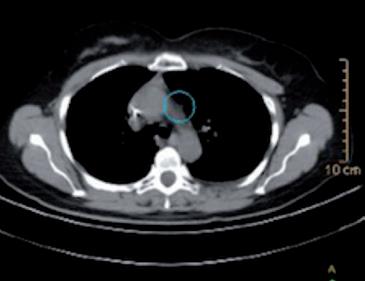

Alla RMN encefalo con mdc di approfondimento venivano evidenziate plurime lesioni ripetitive (almeno 10)

in sede sovratentoriale (diametro massimo 10x12 mm in sede temporale destra) circondate da alone di edema. Ulteriore lesione sospetta in sede sottotentoriale vermiana paramediana destra (2,5x2,5 mm circa) (figura 1a e 1b).

Figura 1a e 1b. Evoluzione della neoplasia mammaria primitiva dalla diagnosi in aprile 2023 alla risposta dopo 7 cicli di T-DXd in aprile 2024.

Figura 2a e 2b. Risposta intracranica completa dopo RT e T-DXd.